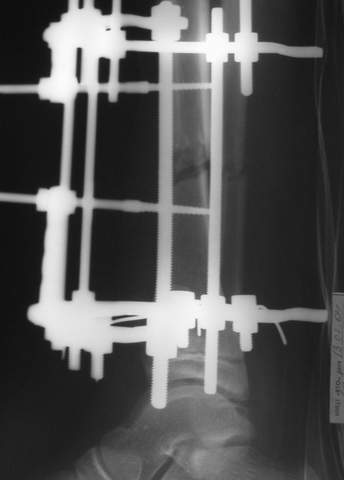

В аттачте № 3 - один из примеров полукольцевого аппарат...

Это уже я баловался.

Итог? Работы больше (по времени и

интраоп "подгонке"), срастается также, а особого преимущества по сравнению с

"чиста" кольцевым (вес, удобство ношения и пр.) - я, по крайней мере,

не нашел.

Теперь не балуюсь.

Может быть зря?